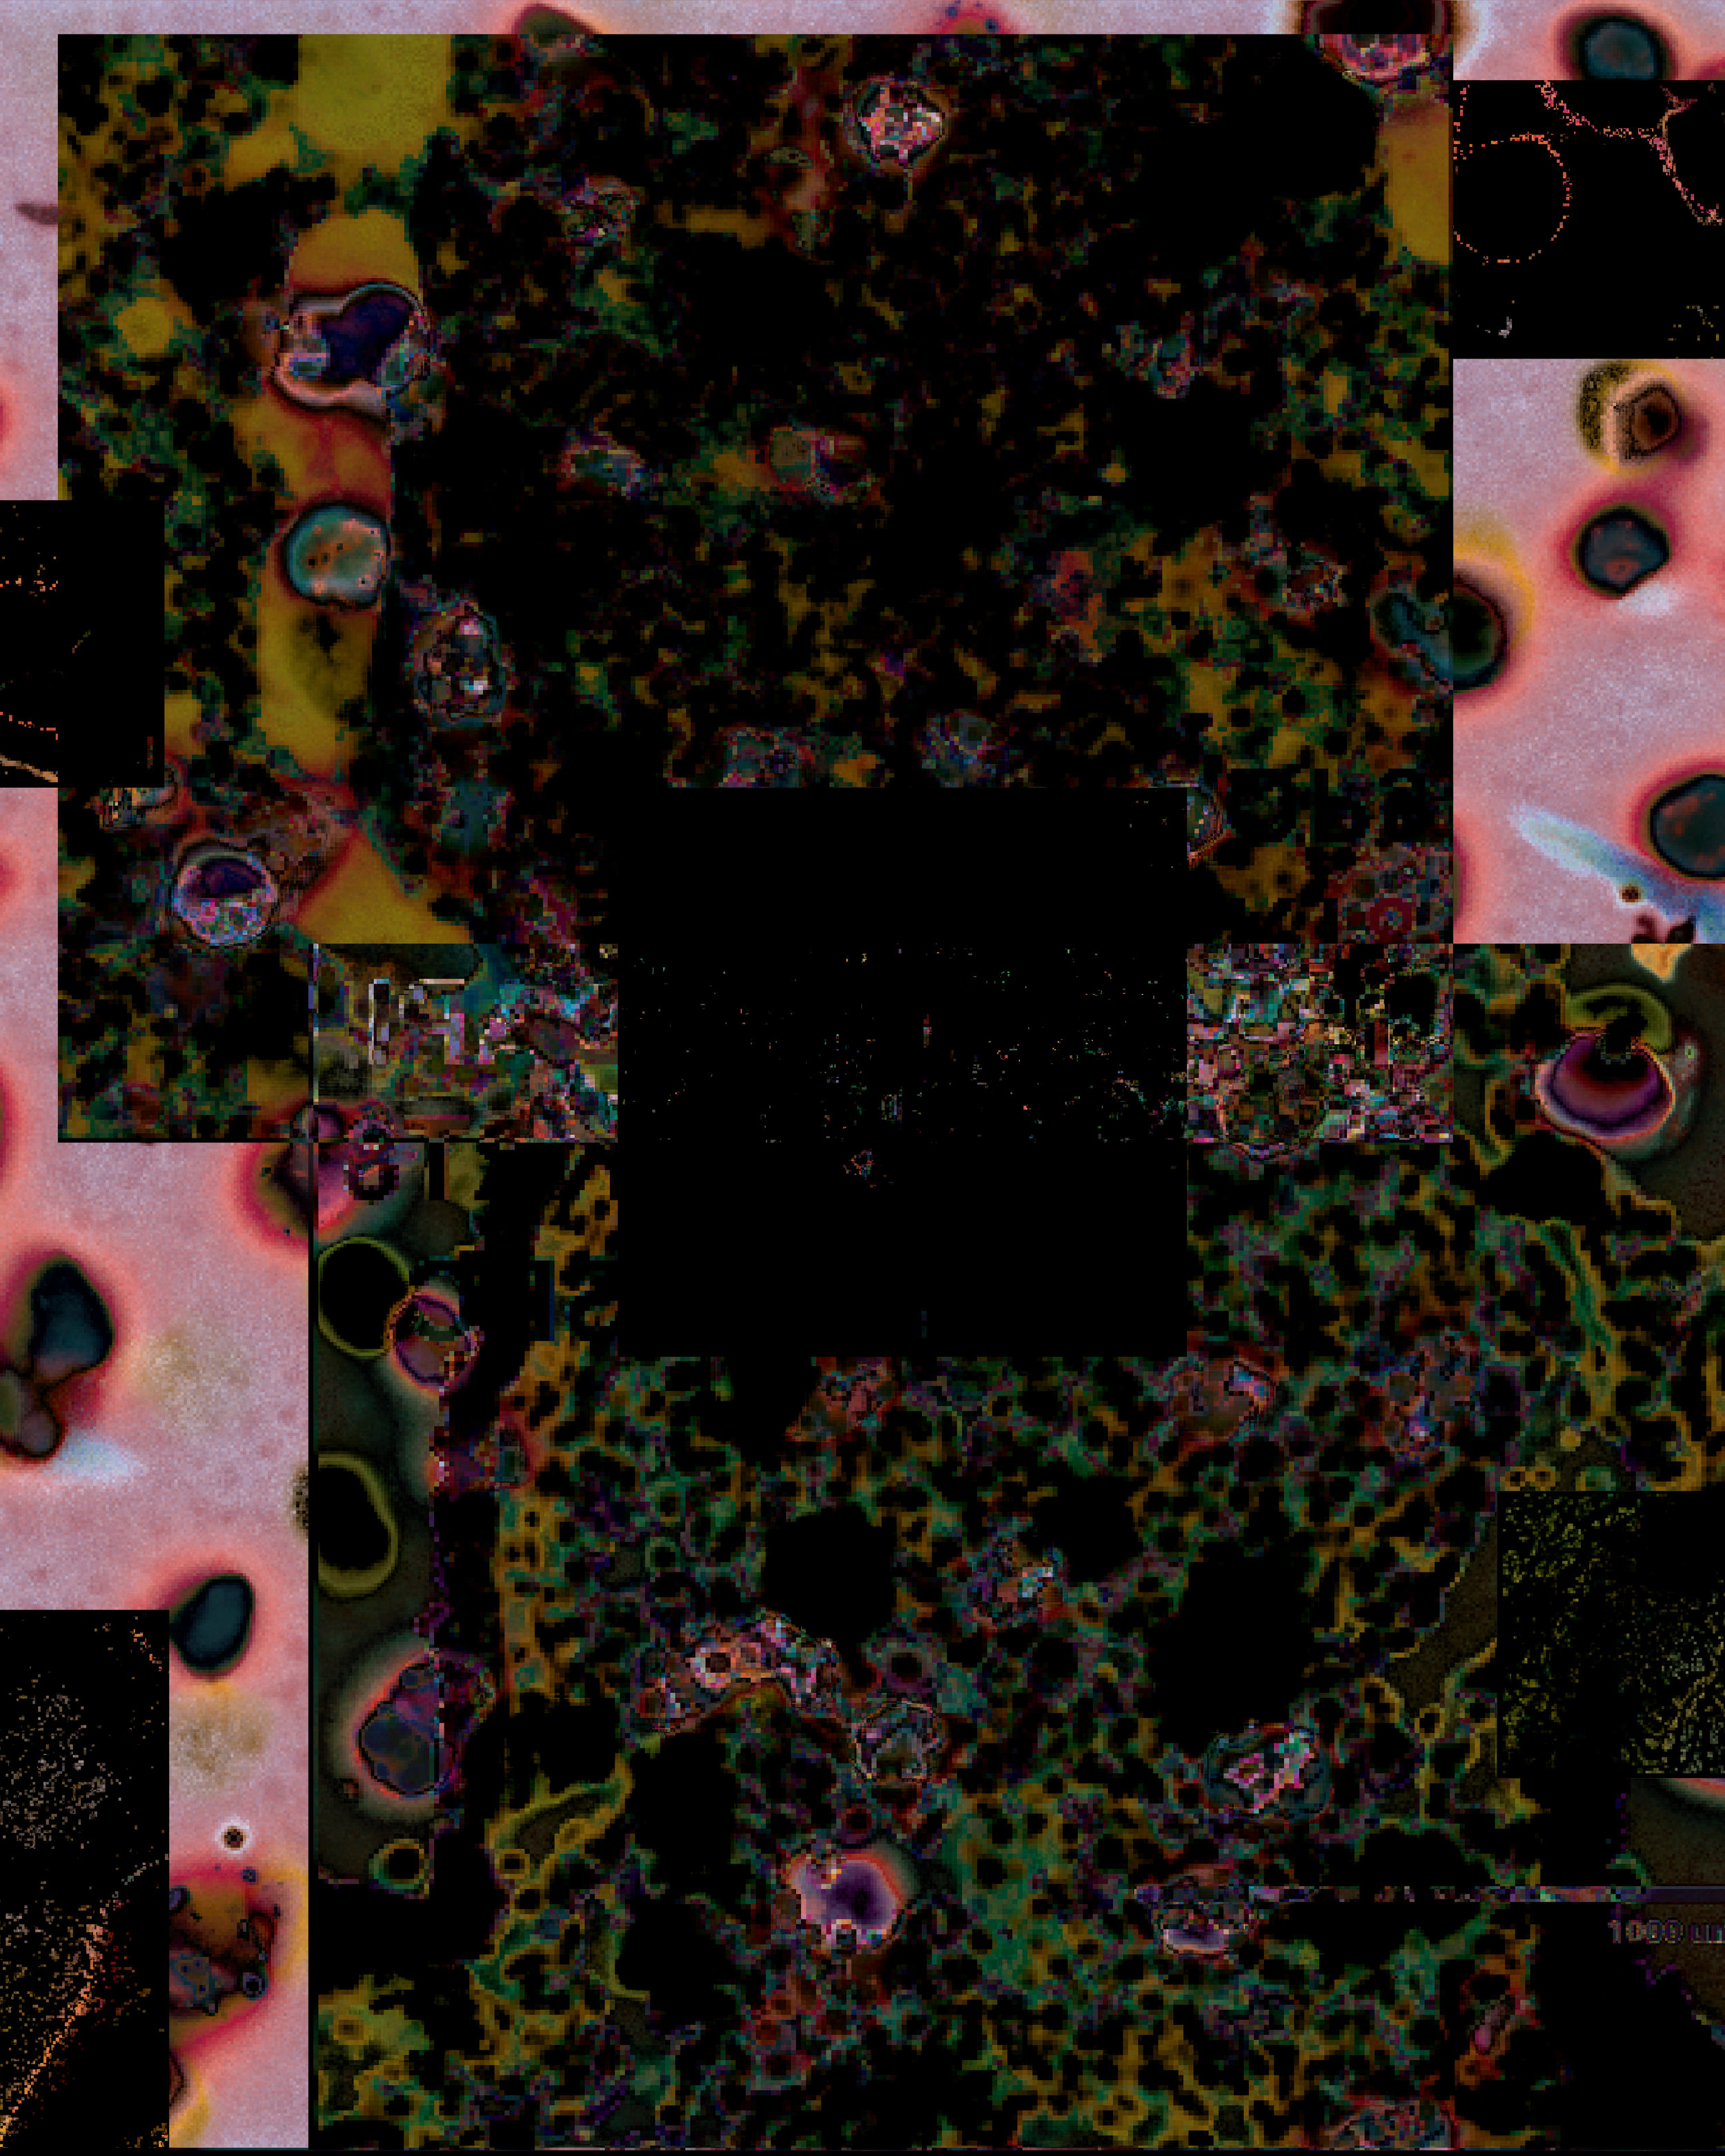

When working with Dr. Crystal Marconet and her research team, we wanted to highlight how lung cancer forms on a cellular level. Dr. Marconett and her team are researching how a specific gene, LNCC0261, can aid in treating lung cancer. Through the use of lung tumor scans, l was able to create a piece that not only shows how and why lung cancer affects the body but also ways it can be treated. Each of the cigarette boxes artwork shows different stages of lung cancer. The first shows an entirely healthy lung, the second a lung with cancer and being treated using the LNCCO261 gene, and the lasta lung with untreated lung cancer. The cigarette boxes themselves represent the main cause of lung cancer today: smoking.